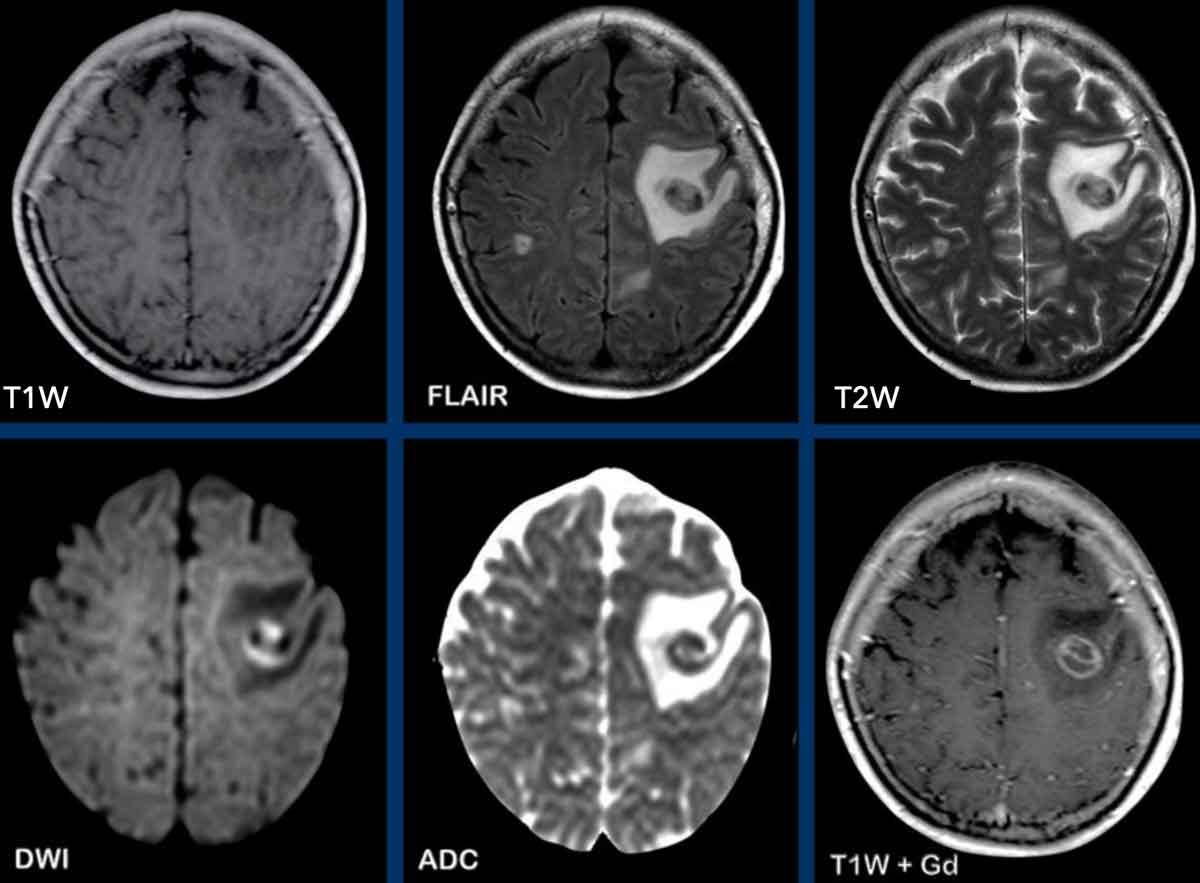

Các hình ảnh này của một phụ nữ 76 tuổi, có biểu hiện lú lẫn sau khi ngã.

Hãy quan sát các hình ảnh trước rồi mới tiếp tục đọc.

Câu hỏi:

- Chẩn đoán có khả năng nhất là gì?

- Những dấu hiệu nào điển hình cho chẩn đoán này?

Các dấu hiệu bao gồm:

- Tổn thương tăng tỷ trọng trên CT không tiêm thuốc cản quang kèm phù não do mạch máu.

- MRI cho thấy nhiều tổn thương ngấm thuốc dạng đặc và hạn chế khuếch tán.

- Trên chuỗi xung T2W, các tổn thương biểu hiện giảm tín hiệu.

- Một tổn thương nằm ở thể chai và một tổn thương khác nằm cạnh não thất.

Tất cả các dấu hiệu này đều điển hình cho u lympho nguyên phát hệ thần kinh trung ương, khác với u lympho hệ thống.

Các khối u này chiếm 6-7% tổng số u hệ thần kinh trung ương và mô học là u lympho tế bào B không Hodgkin.

Chúng thường nằm ở vùng cạnh não thất dưới màng nội tủy, thể chai và hạch nền.

Luôn nghĩ đến u lympho khi gặp tổn thương ngấm thuốc dạng đặc nằm gần não thất.

Hình ảnh tăng tỷ trọng trên CT, giảm tín hiệu nhẹ trên chuỗi xung T2W cũng như hạn chế khuếch tán được giải thích là do mật độ tế bào dày đặc của mô u lympho.

Ở bệnh nhân suy giảm miễn dịch, kiểu ngấm thuốc có thể là dạng vòng nhẫn.

Bệnh nhân này có nhiều phù não, nhưng trong nhiều trường hợp phù não rất hạn chế.